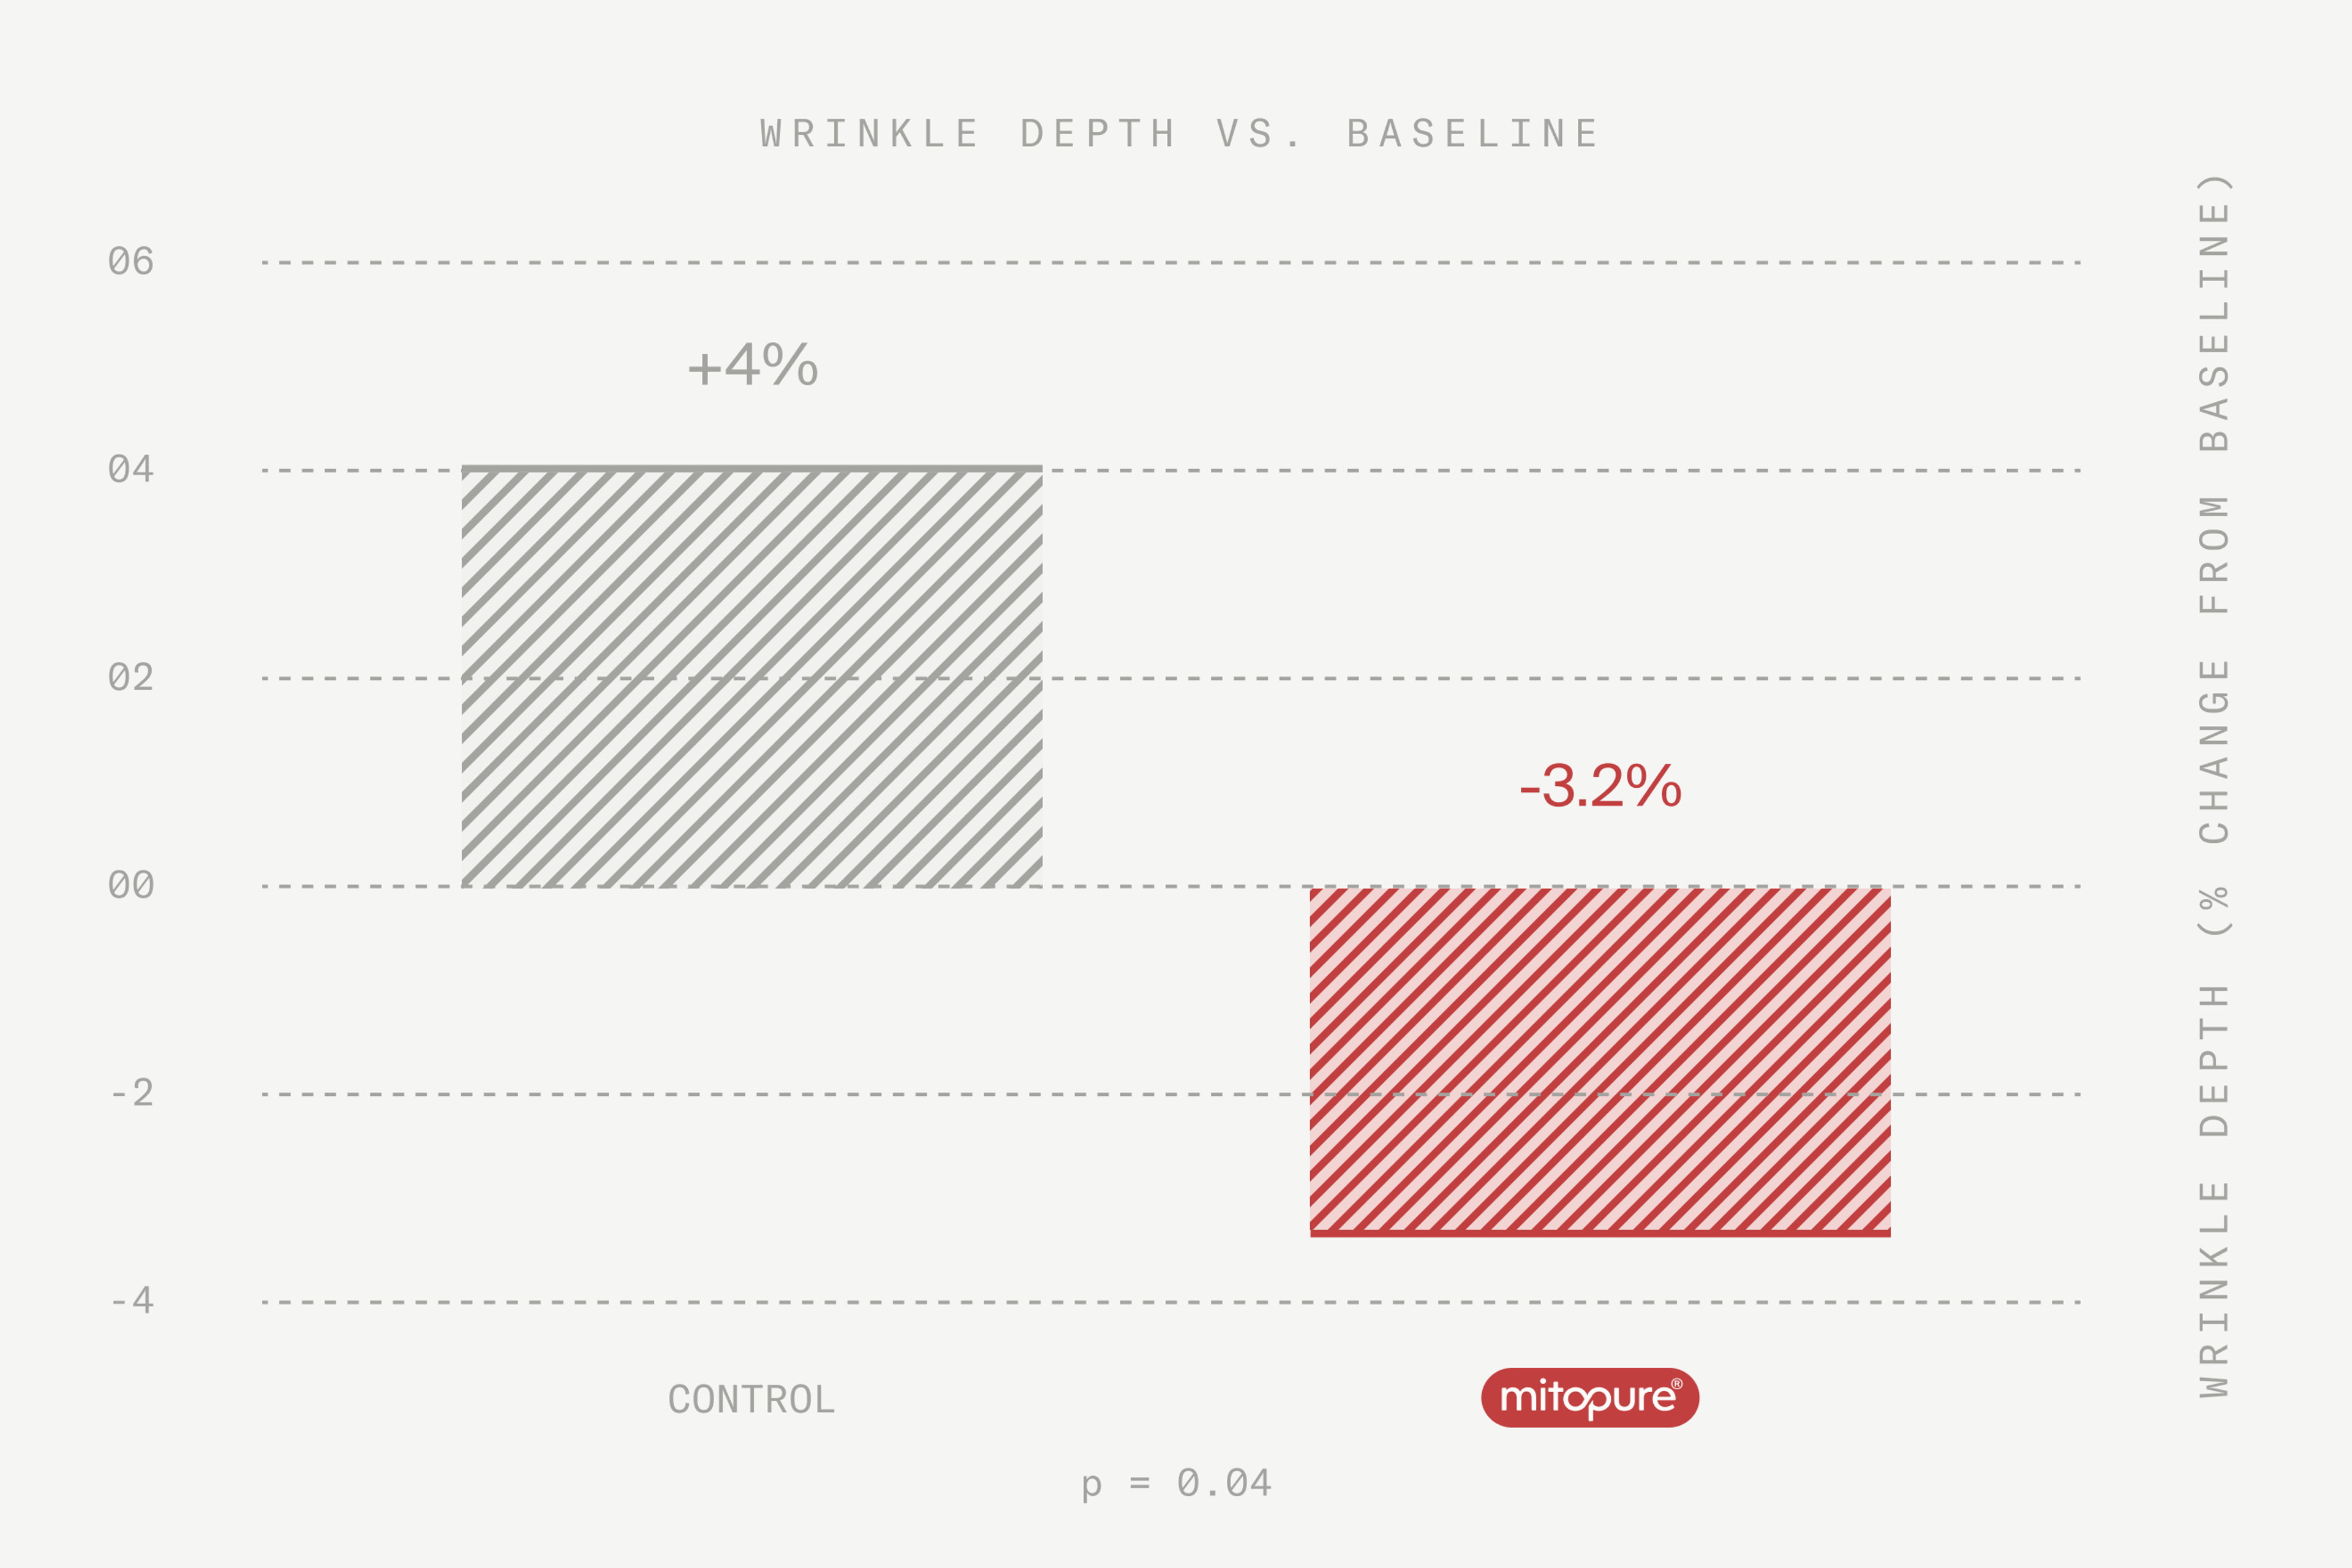

Mitopure® leaves skin with a more youthful appearance

As skin ages, fine lines and wrinkles start to appear. Mitopure® has been proven to start visibly reducing wrinkle depth and volume after only 2 weeks of use.

What’s the evidence? A human clinical study demonstrated that the application of Mitopure® to skin in the area of the crow’s feet (fine lines and wrinkles next to the eye) led to a reduction in wrinkle depth, volume and appearance.

Internal Amazentis study 5: Human clinical trial: Visibly reduces the appearance of fine lines and wrinkles based on a 8-week randomized clinical trial of 48 healthy women aged 50 to 75 years. Twice-daily, morning and evening, application.